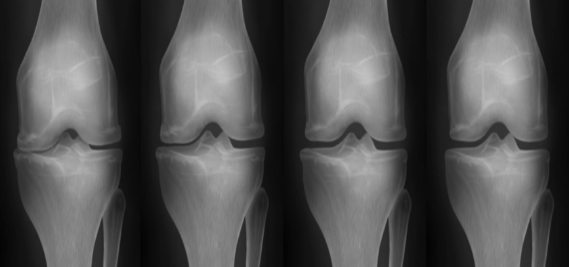

줄기세포 시술 전후 관절 X-ray